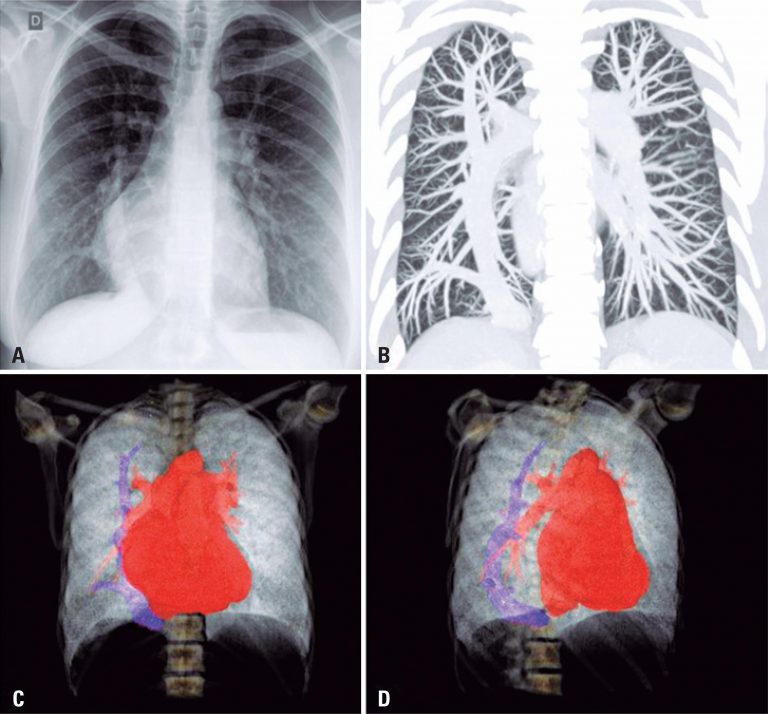

A 49-year-old man came to our emergency department with a 2-day history of fever, cough, anosmia, ageusia and odynophagia. His past medical history included hypertension. At the time of this presentation, chest computed tomography revealed peripheral and bilateral ground-glass opacities, with some visible intralobular lines – typical findings of pneumonia caused by the severe acute respiratory syndrome coronavirus 2 (SARS-CoV-2). In addition, some findings revealed the target sign (). The patient’s supportive treatment was continued, and reverse-transcriptase polymerase chain reaction […]